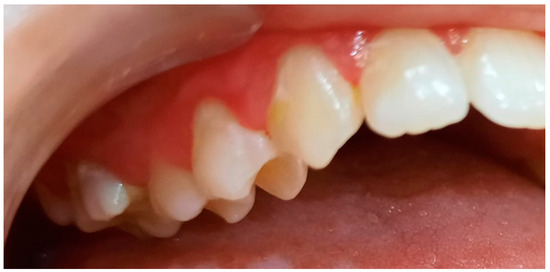

2.2. Clinical Examinations

3.2. Analysis of Clinical Data